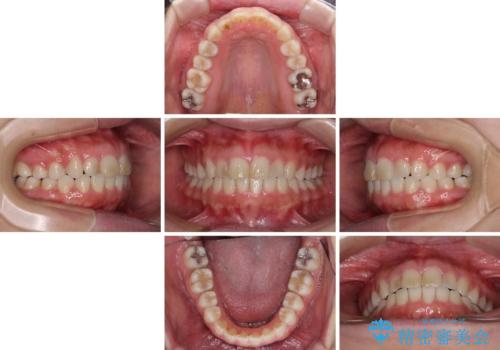

- ワイヤーではない矯正治療があると聞いたとのことで来院された患者様です。

長年前歯のデコボコを気にしていたもののワイヤー矯正に抵抗があり躊躇していたそうですが、インビザラインなら治療してみたいとのことで相談にいらっしゃいました。

インビザライン適用の歯列であったため、歯と歯の間を削るIPRを用いて改善することとしました。

お仕事柄、長時間のマウスピース装着が苦ではなかったので、歯列はすぐに整いましたが、ゆっくりとした交換頻度であったので、2年ほどの治療期間を要しました。